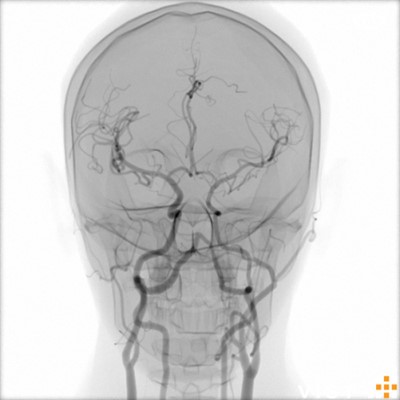

Simuladores Endovanculares.

Aquíhayuna listademódulosundonibles concatibles con el simulador vist g5(Versiónforporidenteyy lab,没有兼容的孔血管y vist灯)。Esta listaestántancoreeevolución,没有Dude en advertarla promicy ... los dutallesestándisponibles haciendo clic en eltítulodelmódulo(网站蒙黛尔,enInglés)